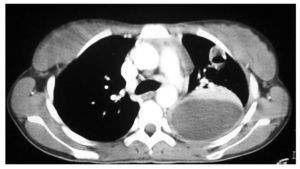

Fig. 2. Tomografía computarizada de tórax.